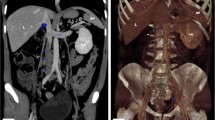

Duplex sonography of the right limb showed an epifascial thrombophlebitis that barely reached the crossing veins without deep venous thrombosis. A pulmonary embolism was ruled out by a CT-Angiography of the chest. The additional computer tomography of the abdomen and pelvis revealed an abnormal inferior caval vein which was fed just by the hepatic veins. The blood of the extremities and the kidneys was drained over a varicose venous plexus equivalent to the thoracic venae azygos and hemiazygos. In the sense of a bypass circulation the umbilical vein was recanalized, and varicose veins of the abdominal wall were apparent (Fig. 1). The superficial femoral vein on the left side was filled by a probably old thrombus which reached the varicose network in the pelvis (Fig. 2). The right kidney was atrophic (Figs. 1, 3). We diagnosed an epifascial thrombophlebitis of the right leg with missing lower IVC and atrophic right kidney. The history of idiopathic deep vein thrombosis and the present thrombophlebitis could now be explained by the atresia of the inferior caval vein. It has been suggested that this anatomical situation contributes to a prothrombotic situation due to stasis of the blood for lack of sufficient drainage through the azygos and hemiazygos veins [14].